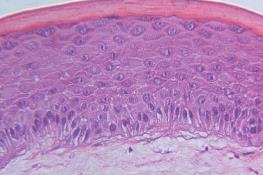

درمان سرطان پوست با پوست مصنوعی

محققان دانشگاه «کپنهاگ» دانمارک در مطالعه اخیرشان اظهار کردند، پوست مصنوعی می‌تواند راه را به سوی درمان‌های جدید برای سرطان پوست هموار کند.